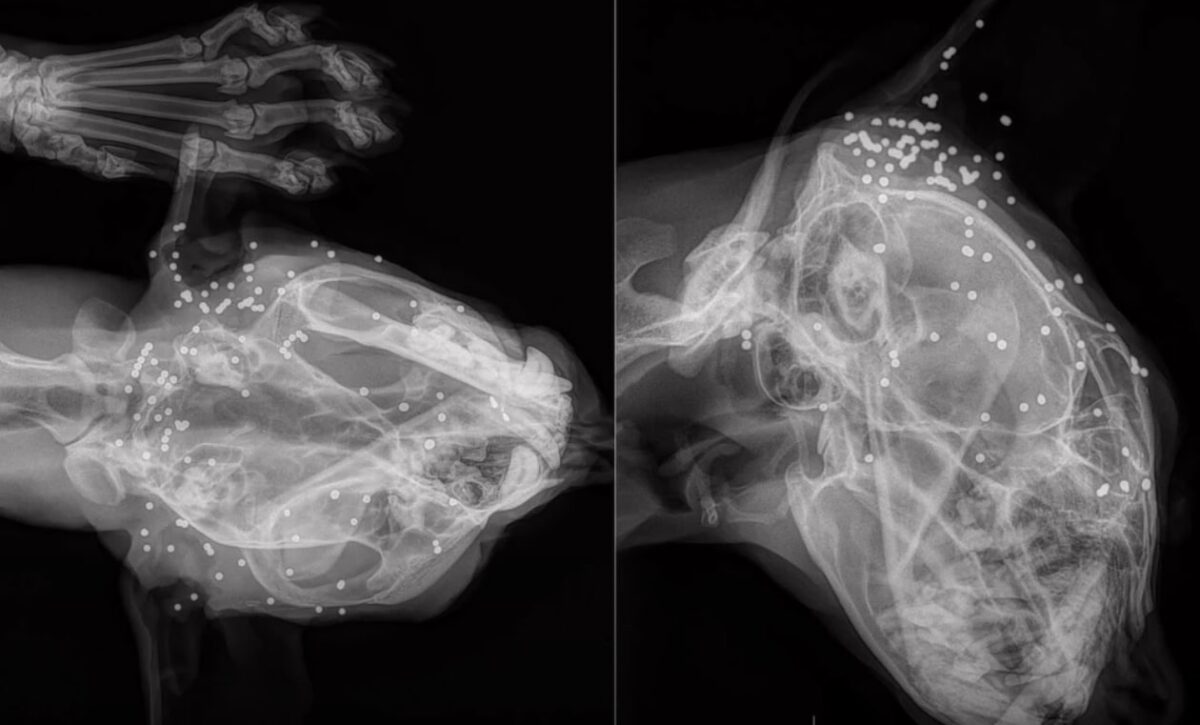

Deux tirs illégaux, un oeil crevé, l'autre blessé

Trois jours plus tard, les équipes du centre parviennent à retrouver et capturer l’animal et découvrent qu’il s’agit en réalité d’une femelle adulte "tellement maigre qu’elle en paraissait petite". Après un examen vétérinaire approfondi, le résultat est sans appel. L'animal aurait subi deux tirs illégaux dont un remontant à trois semaines. Celui-ci lui aurait d’ailleurs crevé l’oeil gauche. De plus, l’oeil droit aurait été récemment blessé à la suite d'"un choc localisé avec un objet contondant" pouvant correspondre au "caillassage" signalé. Une "quadruple peine" pour cette femelle dont les jeunes, actuellement recherchés, "sont en danger de mort" rappelle l'association.

Habilité à soigner et rééduquer les lynx blessés ou orphelins avant de les relâcher dans leur milieu naturel, le centre Athénas a pu prendre en charge l’animal dès sa capture. Gilles Moyne, le directeur du centre, nous a toutefois confié qu’il ne savait pas aujourd’hui s'il allait pouvoir être sauvé. Les équipes du Centre Athénas sont actuellement à pied d’oeuvre pour tenter de sauver son oeil droit. À ce jour, la jeune femelle est encore loin d’être tirée d’affaires.